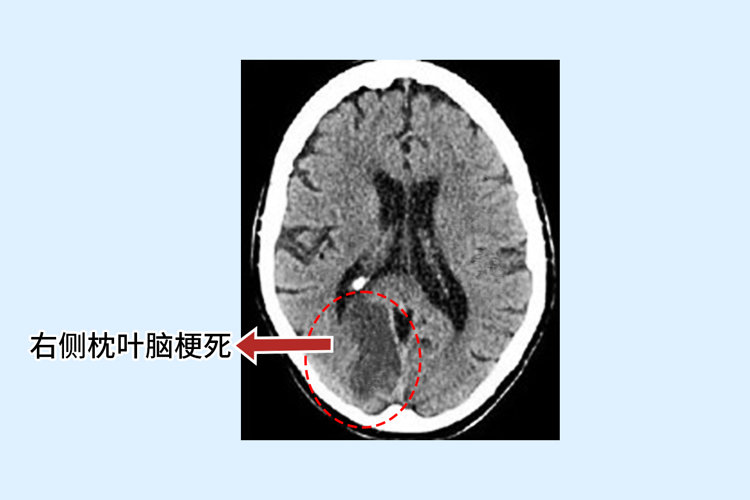

2024-04-01王大叔今年61岁,罹患高血压多年时间,这两年来血压一直控制的不是很稳定。一天深夜,他突发脑梗整个人失去了意识,送去医院检查时发现